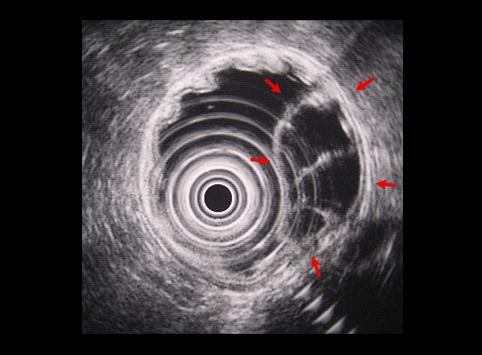

A case of a cystic tumor with septa which developed in the stomach.

Non-epithelial tumors/Cyst

Ultrasonography

40 -